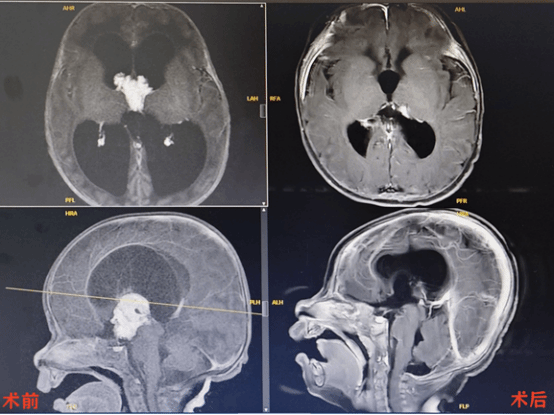

术前,三脑室内血供极其丰富的肿瘤,重度脑积水;术后半年复查,肿瘤全切,脑室轻度扩大,基本恢复正常

进一步寻找原因病因,最终头颅的增强MRI锁定了“元凶”:倩倩第三脑室深处,一个形如菜花、血管密布的3厘米肿瘤正在疯狂“放水”。更致命的是,肿瘤完全堵塞脑脊液循环通路,形成“双重脑积水”——既过量产水,又阻断排水,每日新增加约20毫升脑脊液,头颅如同持续加压的高压锅。